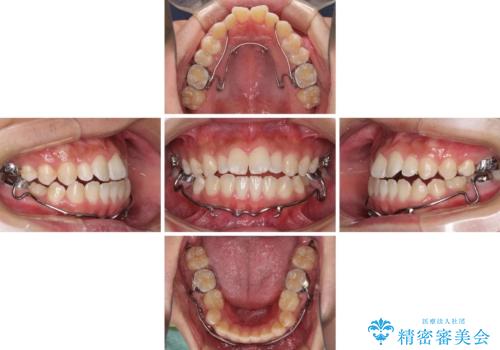

口元の突出感を改善 受け口傾向の咬み合わせの抜歯矯正

- メタルブラケット

- 受け口傾向の咬み合わせと口元の突出感を気にして来院された患者様です。

受け口傾向特有の狭い上顎歯列であったため、歯列の拡大を補助装置で行い、下顎歯列全体を後方に移動させることとしました。

奥歯の咬み合わせを改善させた後、上下左右の小臼歯(下顎は残存乳歯)を計4本抜歯し、ワイヤー装置にて口元の突出感を改善しながら咬み合わせを整えることとしました。

下顎の残存乳歯は小臼歯よりも大きいため、スペースを閉じるために長い期間を必要としますが、予想通りに長期間を要することとなりました。

受け口傾向の方の抜歯矯正は、下顎前歯が舌側に倒れることで歯肉退縮を起こしやすいことが知られていますが、ワイヤーに工夫をすることでリスクを軽減させています。